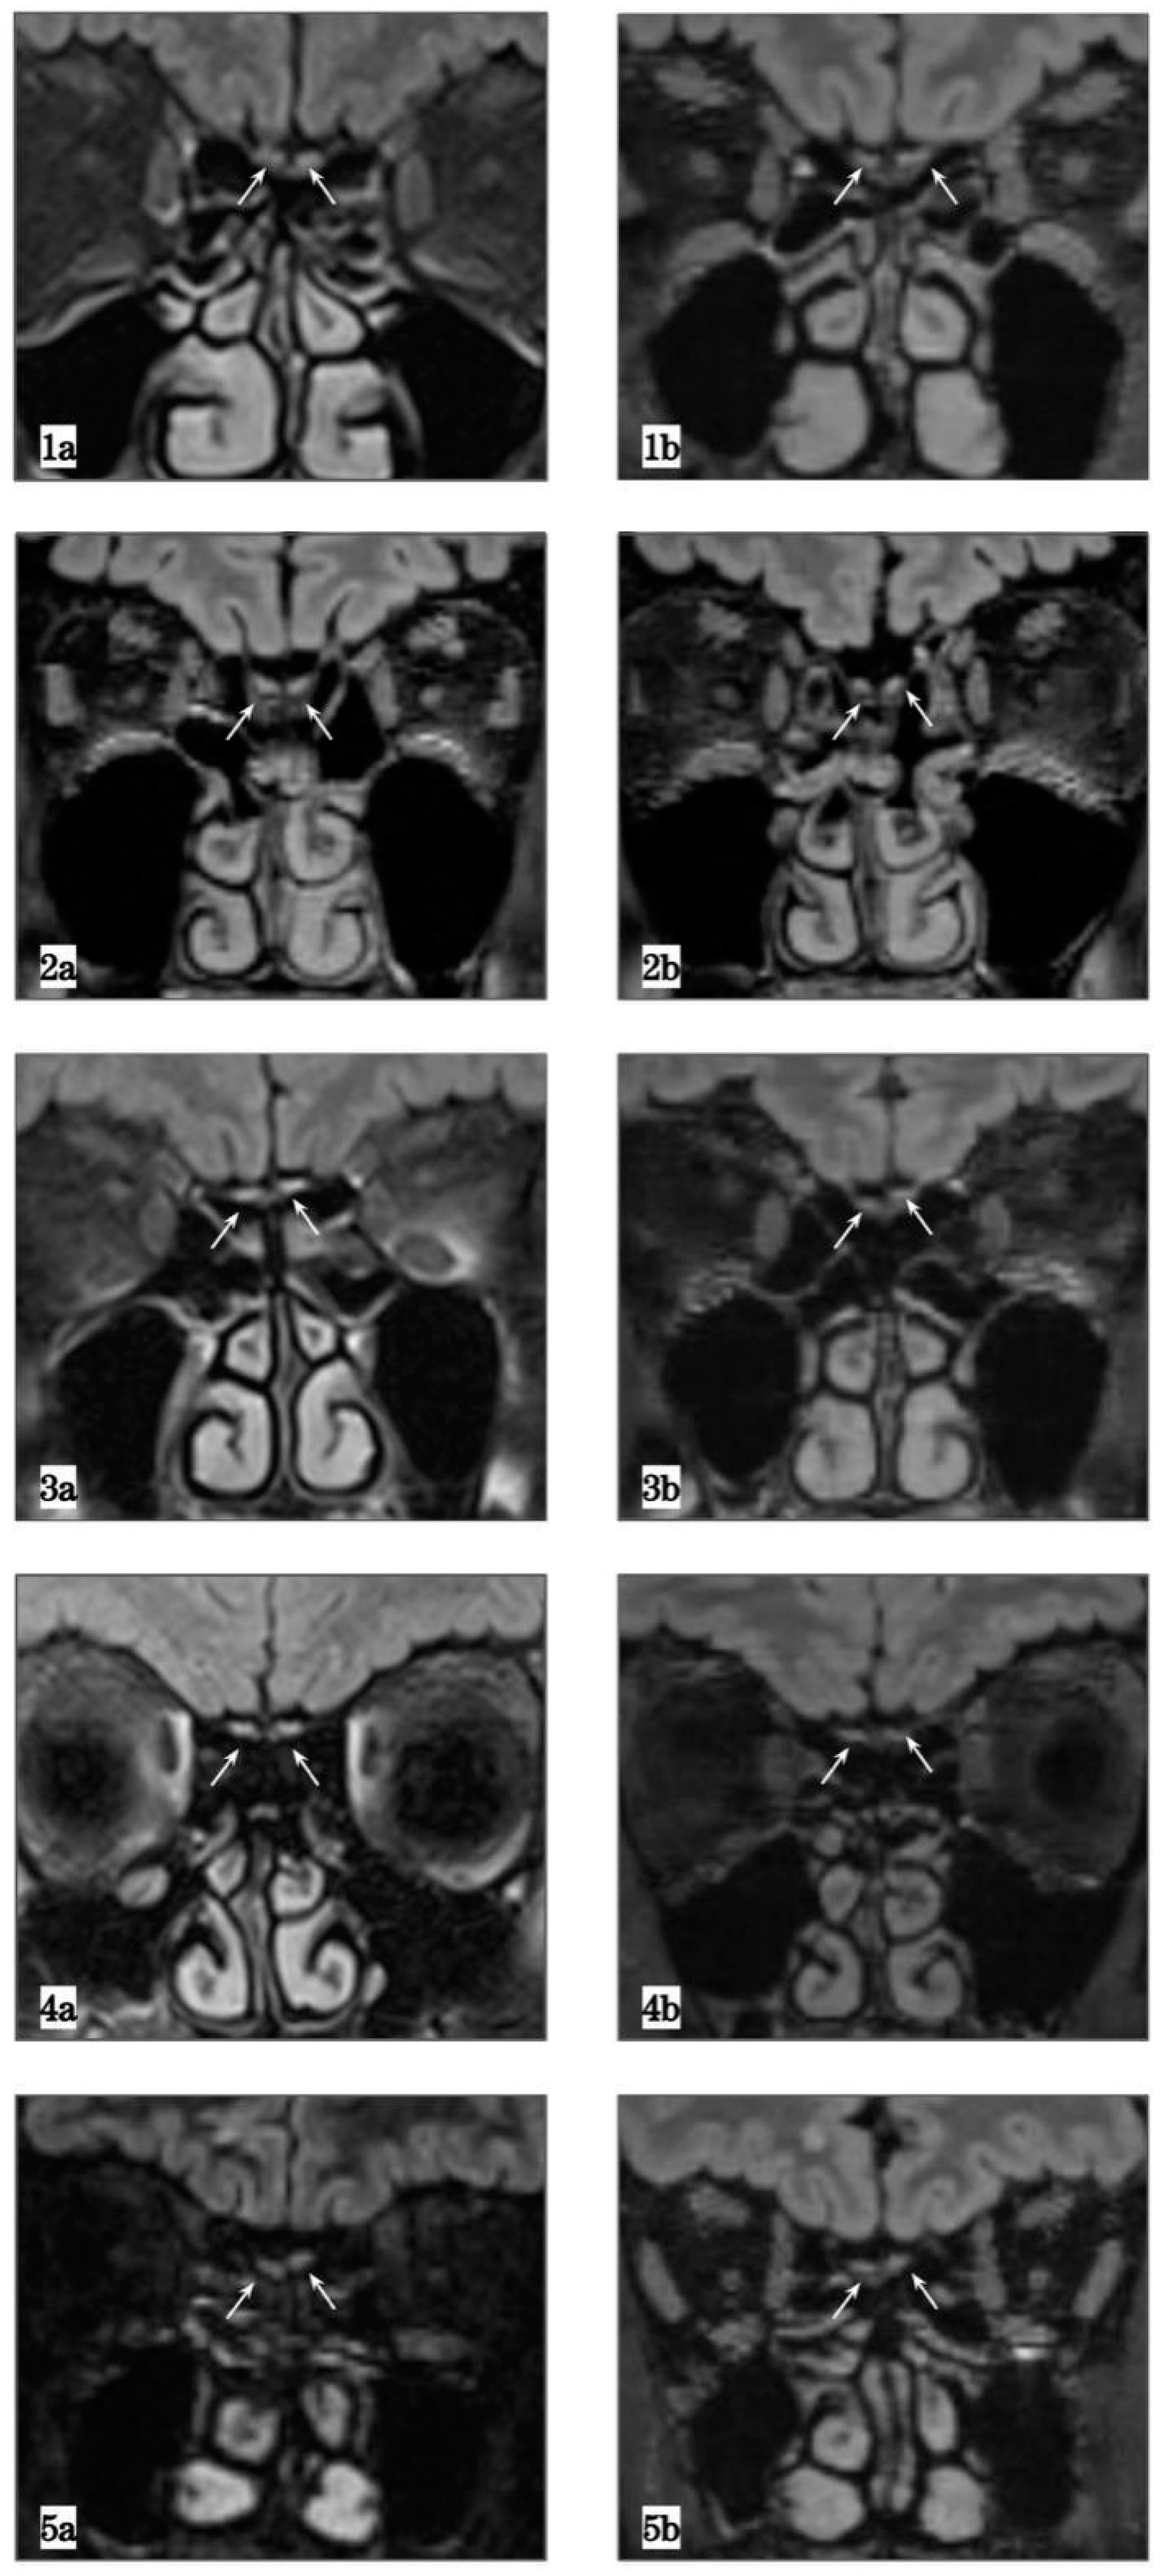

| Case Number | Age, Gender | Sniffin’ Sticks Test | Before COVID-19 Left OBV (mm3) | After COVID-19 Left OBV (mm3) | Before COVID-19 Right OBV (mm3) | After COVID-19 Right OBV (mm3) |

|---|---|---|---|---|---|---|

| Case 1 | 70, M | 23/48 | 86.96 (1a) | 26.07 (1b) | 69.4 (1a) | 26.99 (1b) |

| Case 2 | 70, M | 25/48 | 77.42 (2a) | 37.24 (2b) | 81.36 (2a) | 44.94 (2b) |

| Case 3 | 59, F | 32.5/48 | 75.55 (3a) | 28.33 (3b) | 58.25 (3a) | 19.44 (3b) |

| Case 4 | 23, F | 30.5/48 | 105.44 (4a) | 55.04 (4b) | 116.4 (4a) | 45.93 (4b) |

| Case 5 | 45, M | NA | 40.58 (5a) | 48.3 (5b) | 53.53 (5a) | 66.87 (5b) |